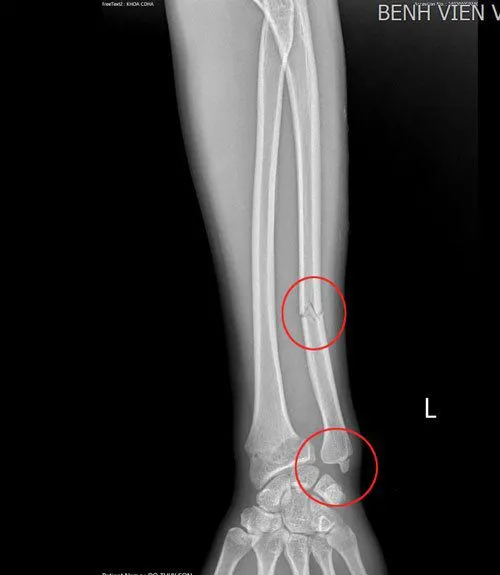

Thông tin từ Bệnh viện Việt Nam - Thụy Điển Uông Bí (Quảng Ninh) cho biết, một phụ nữ 28 tuổi vừa nhập viện cấp cứu sau khi bị ngã do áo chống nắng bị cuốn vào bánh xe máy trong quá trình di chuyển. Sau khi tiến hành chụp chiếu, phát hiện nữ bệnh nhân này bị gãy tay. Hiện đã tiến hành phẫu thuật và tình trạng sức khỏe đang ổn định, tiếp tục được theo dõi.

Hình ảnh gãy xương của cô gái (Ảnh: BVCC)